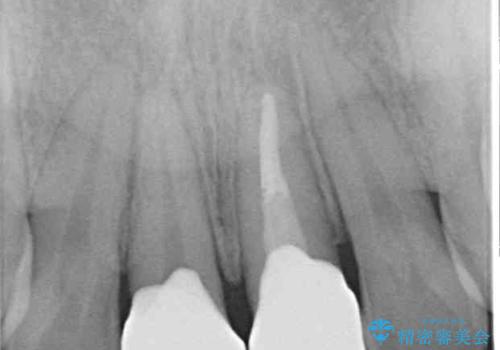

インビザラインでの矯正治療がそろそろ終了とのことで、新しいインビザラインセットを発注する前に気になっている前歯2本をオールセラミッククラウンにて補綴治療を行うこととしました。

歯肉の腫脹は大分改善されましたが、なかなかご自身でのブラッシングが上達せず、やや腫脹残った状態での治療終了となりました。